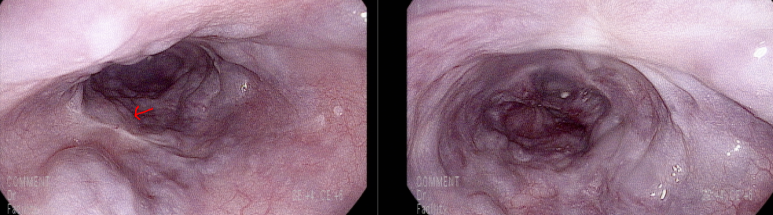

이번 검진 내시경, 이전과 같은 위치에 결찰술 흔적

하부 식도에 추가로 결찰술한 흔적

그러나 전체적으로 LsF3CbRCS(+++) 정도의 소견은 변화없음